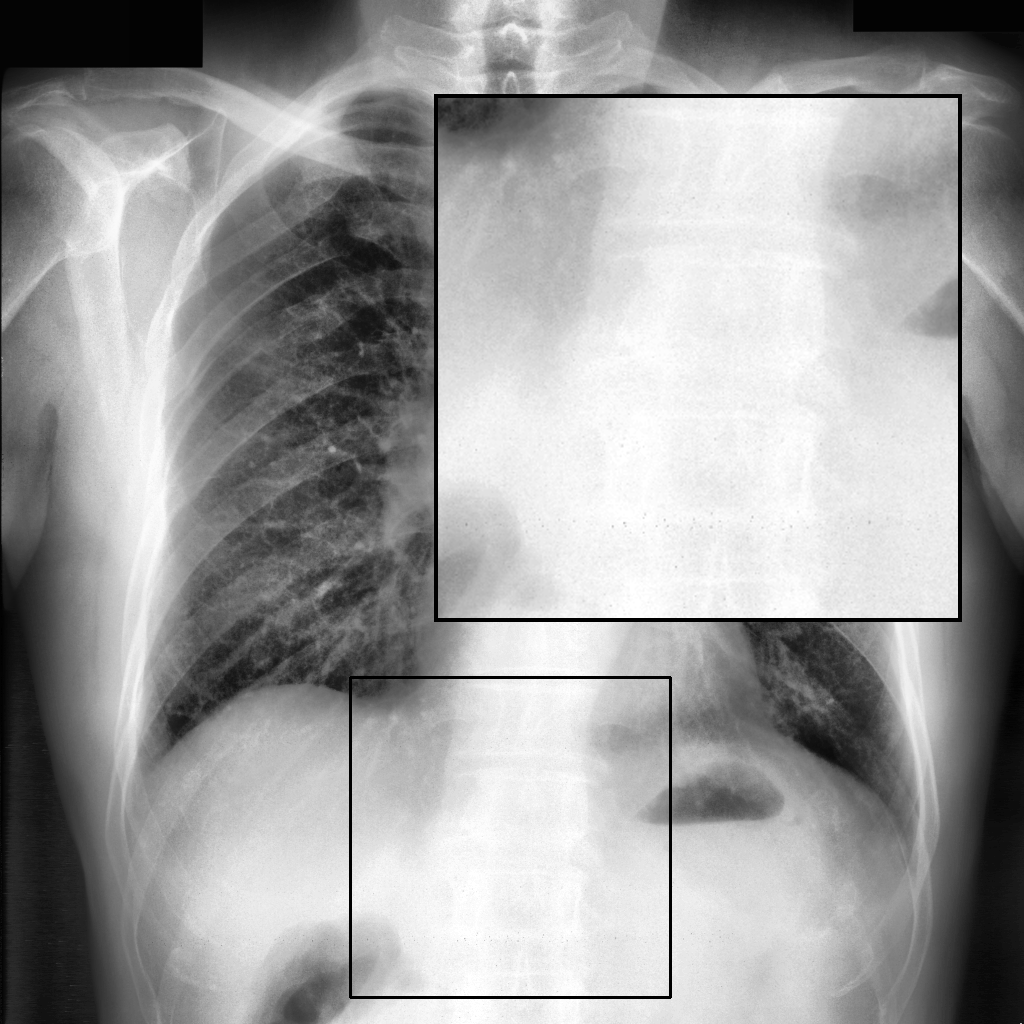

Fig. 3 shows image samples from the above datasets.

Figure 3: Image diversity across four datasets: (a) JSRT, (b) Montgomery County X-ray, (c) NIH ChestX-ray14, and (d) CheXpert